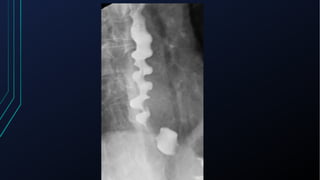

Trato Gastrointestinal

• Esofagite de Refluxo

• Espasmo Esofagiano Difuso

• Ruptura esofágica

• Úlcera Péptica

• Colecistopatia calculosa

• Pancreatite